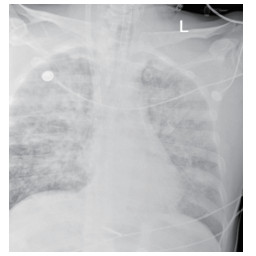

1.2 临床表现和检查患者初期有咳嗽症状,但未在意,患者回家24 h后咳嗽症状加重,伴胸闷气喘,全身大汗淋漓,家属立即将其送至本院急诊,为进一步诊治拟“有机氟中毒”收住入院。入院时体检:神志清楚,T:36.5℃,R: 57次/min,BP: 146/71 mmHg,胸廓对称无畸形,呼吸急促,听诊双肺呼吸音清晰,可闻及大量湿性啰音,心率112次/min,心律齐,心音正常,各瓣膜听诊区未闻及病理性杂音及心包摩擦音,四肢关节正常,双下肢无水肿,深浅生理反射正常,病理反射阴性,脑膜刺激征阴性。辅助检查:白细胞计数10.45×109/L,中性粒细胞91.9%;C-反应蛋白14.81 mg/L, 无创机械通气支持下血气分析pH7.28,PCO2 50 mmHg, PO2 57 mmHg, Lac 3.0 mmol/L(FiO2 50%),为Ⅱ型呼吸衰竭,给予无创呼吸机辅助呼吸、激素冲击、解痉平喘等抢救治疗。急诊胸部CT检查提示:两肺散在斑片状模糊影,密度不均,边界不清(图 1),进ICU床边胸片提示:两肺散在斑片状模糊影(图 2)。根据GBZ5—2016《职业性氟及其无机化合物中毒的诊断》的诊断标准,该患者诊断为职业性急性重度有机氟中毒。

| 图 2 3月10日胸部X线 |

该患者入院后因氧合不能维持、呼吸窘迫直接从急诊收治ICU,大剂量激素冲击及气管插管,呼吸机SIMV+PS模式支持治疗,氧合指数改善不明显,及时行俯卧位通气,但氧合指数仍然小于100,PAO2 38 mmHg, SpO2 78%左右,考虑患者病情危重,且血流动力学不稳,血管活性药剂量大,当天下午行V-V模式ECMO治疗(右侧颈静脉-右侧股静脉),血流速度3.5 L/min,氧流量3.5 L/min,氧体积分数50%,行保护性机械通气,通气模式是压力控制(PC 15 cmH2O,PEEP 8 cmH2O,FiO2 50%,f 12次/min), 镇痛镇静,RASS评分在-4~-5分,必要时阿曲库铵静脉推注行肌肉松弛治疗。其他治疗:甲强龙500 mg治疗3 d,然后逐渐减量;乙酰半胱氨酸抗氧化、化痰、CRRT等支持治疗。ECMO治疗后生命体征明显改善,治疗第2天,血管活性药逐渐减量。治疗3 d后,循环稳定,停用血管活性药,床旁胸片提示:两肺弥漫渗出性改变,较前明显好转。患者症状好转,调节ECMO参数:血流速3 L/min,气体流速3 L/min,氧体积分数35%,控制SpO2 95%~100%之间。在ECMO治疗期间根据血流动力学和血气分析结果不断调整ECMO参数,在ECMO治疗5 d后,脱离ECMO,通气模式改为SIMV+PSV并过渡到PSV(PS 16 cmH2O,PEEP 5 cmH2O,FiO2 30%),氧合良好,在脱离ECMO 2 d后停呼吸机,停机1 d后拔除气管插管。行胸部CT检查示:两肺散在炎性病变,双侧胸膜腔积液(图 3),床旁胸片提示两肺炎性病变(图 4),两肺弥漫性渗出明显改善。后经1周治疗,查胸部CT示:右肺中下叶及左肺少许慢性炎性改变(图 5),病情稳定转至呼吸科病房。